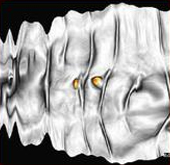

CT Colonoscopy with automatic colon area extraction from abdominal CT image. Display switchable to ?cruising?, ?3 section? and ? panorama mode.

Color and display to process possible. Shape analysis filter (colored polyp on panoramic image)